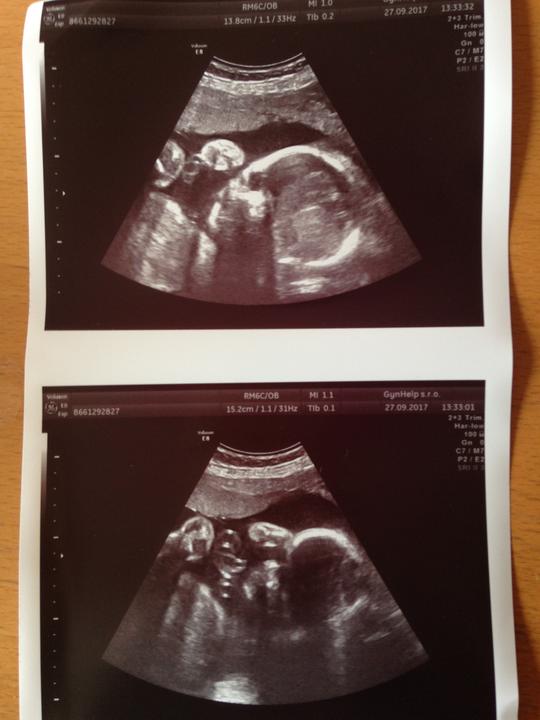

Čekáme holčičku podle všeho 💋💋💋❤️😄🤰🏻🤰🏻